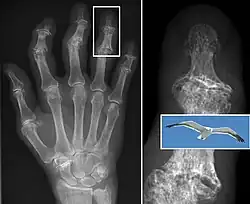

The formation of hard knobs at the middle finger joints (known as Bouchard's nodes) and at the farthest joints of the fingers (known as Heberden's nodes) is a common feature of osteoarthritis in the hands. | |

In smaller joints, such as at the fingers, hard bony enlargements, called Heberden's nodes (on the distal interphalangeal joints) or Bouchard's nodes (on the proximal interphalangeal joints), may form, and though they are not necessarily painful, they do limit the movement of the fingers significantly. Osteoarthritis of the toes may be a factor causing formation of bunions,[16] rendering them red or swollen.

- Bone (left) and clinical (right) changes of the hand in osteoarthritis